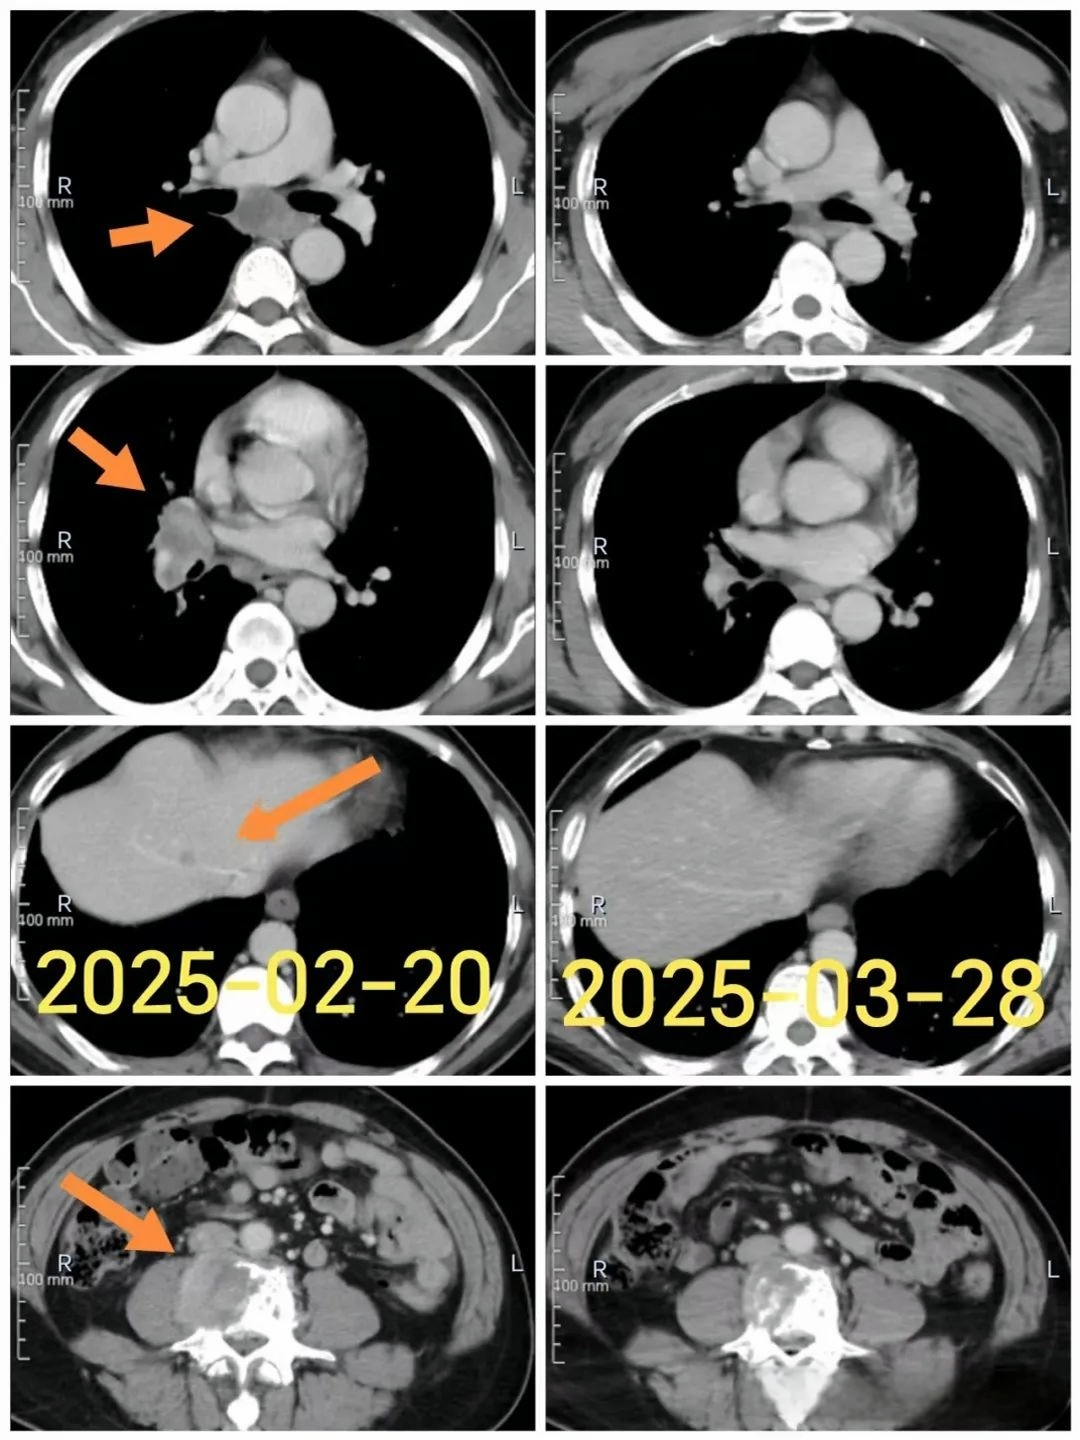

自2月份入组,采用试验药治疗,至今刘先生已经坚持了五个半月。他用的是口服药,几乎没有感觉到有什么药物的不良反应。“这药吃下去,没啥特别的感觉,不像化疗那样难受。” 在最近一次的疗效评估中,刘先生笑着说,“虽然检验检查多了点,但每次看到病灶一点点缩小,心里就踏实多了。”

“用药仅一个月,效果就非常显著,肿瘤明显退缩。” 周俊主任在评估时说,“这是我们中心第一例采用该方案治疗的患者,结果真是令人振奋。他的生活质量也有了显著提高,没有任何不良事件发生。”

图:刘先生影像报告对比

对于NUT癌,周俊主任进一步解读道:“NUT癌好发于中青年,中位生存时间仅为6个月左右,预后极差,目前尚无有效的治疗方法。其主要的发病机制可能是NUTM1基因与参与转录调控的基因融合后,形成了一组肿瘤的致癌驱动因素,促进肿瘤的发生发展。刘先生的情况,就是典型的NUT癌表现。”